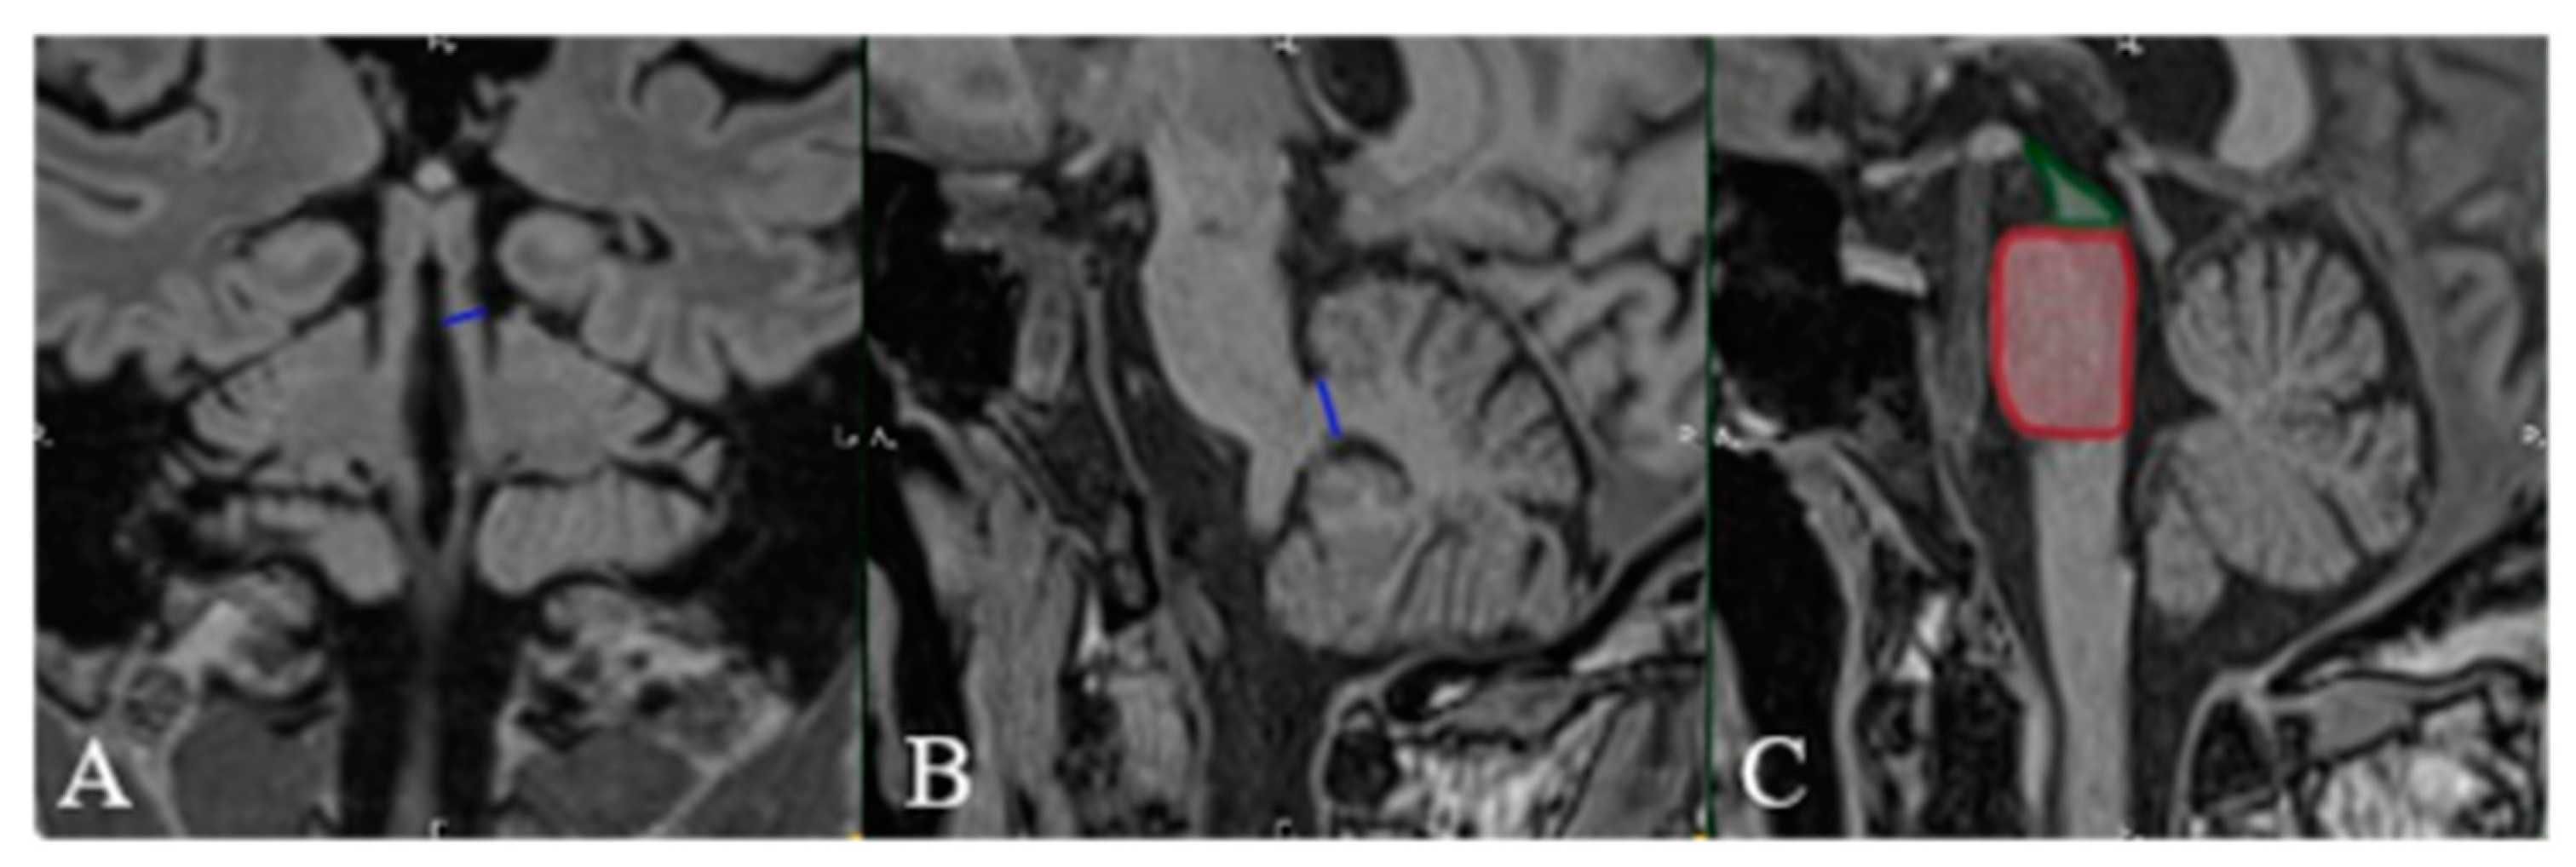

| Positive “hummingbird” sign. |

| Positive “Mickey mouse” sign. | ||||

| Positive “horning glory” sign. | ||||

| MRPI > 14. | ||||

| Midbrain-to-pons ratio = 0.37. | ||||